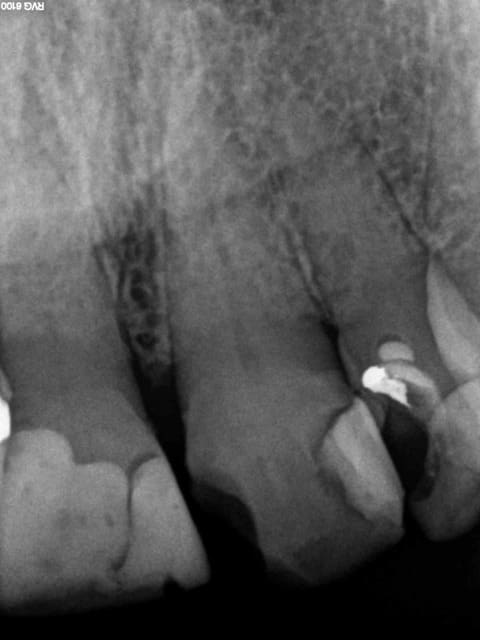

11 21 de la balle crjq1n - Eugenol

Pose 2 ic coiffe 10 mn mxgarl - Eugenol

11 21 endo turbo so1akt - Eugenol